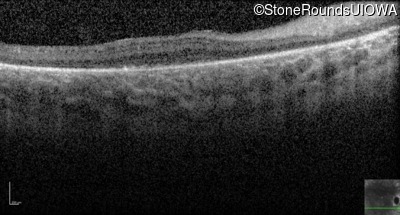

Optical Coherence Tomography - Left - Hand Motion 6" sc

Exemplar / OCT Stack